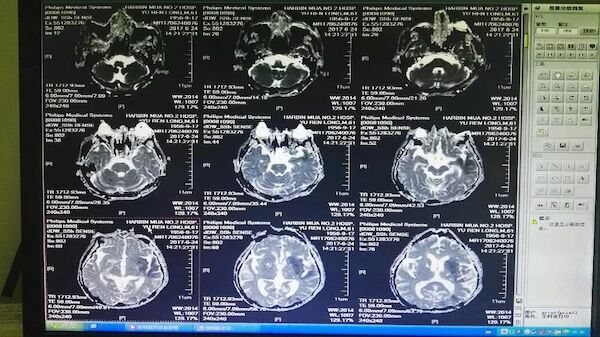

于某,男患,60岁,既往吸烟饮酒史,否认高血压、糖尿病病史,否认心脑血管病病史,入院心电图显示无房颤,2017年6月24日10点左右劳动中起病,突发言语不清,右半身无力,发病5小时,Nihss评分15分,行多模核磁小时左侧大脑中动脉急性闭塞,DWI和ADC显示仍然有可挽救的半暗带,发病6小时全麻下股动脉穿刺,取栓一次成功!

手术前的CT和多模MR